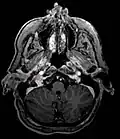

Ectopic functional paraganglioma (glomus jugulare) in a patient with VHL. T2 weighted MRI at the same location demonstrates a high signal mass consistent with a paraganglioma. Extra adrenal paragangliomas can be found in VHL (arrow).